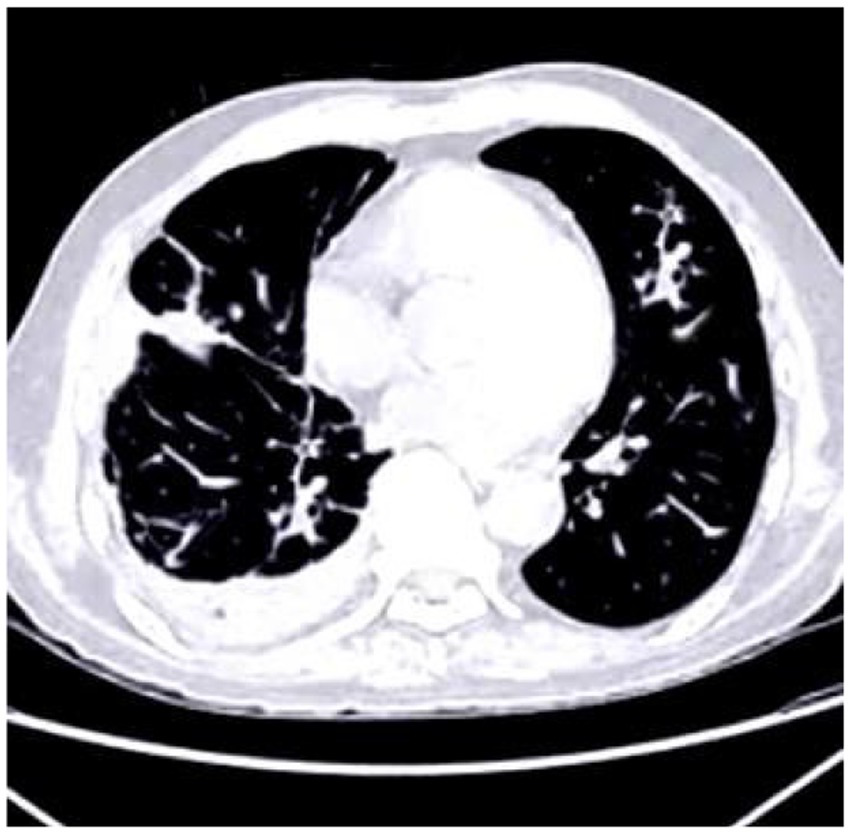

The deposition of calcium within coronary arteries and cardiac tissues gives rise to artifacts that can compromise the accuracy of diagnostic interpretations. Figure 1 shows the cardiac CT image. These artifacts manifest as streaks or shadows, obscuring adjacent structures and impeding the delineation of subtle abnormalities.

Figure 1

Cardiac CT image illustrating the impact of calcium buildup in the coronary arteries. The resulting artifacts, such as streaks and shadows, interfere with the visualization of nearby structures and complicate the detection of subtle cardiac abnormalities.